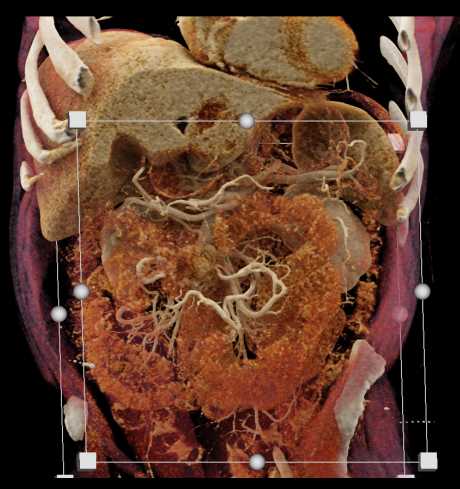

Carcinoid Tumor with Desmoplastic Reaction